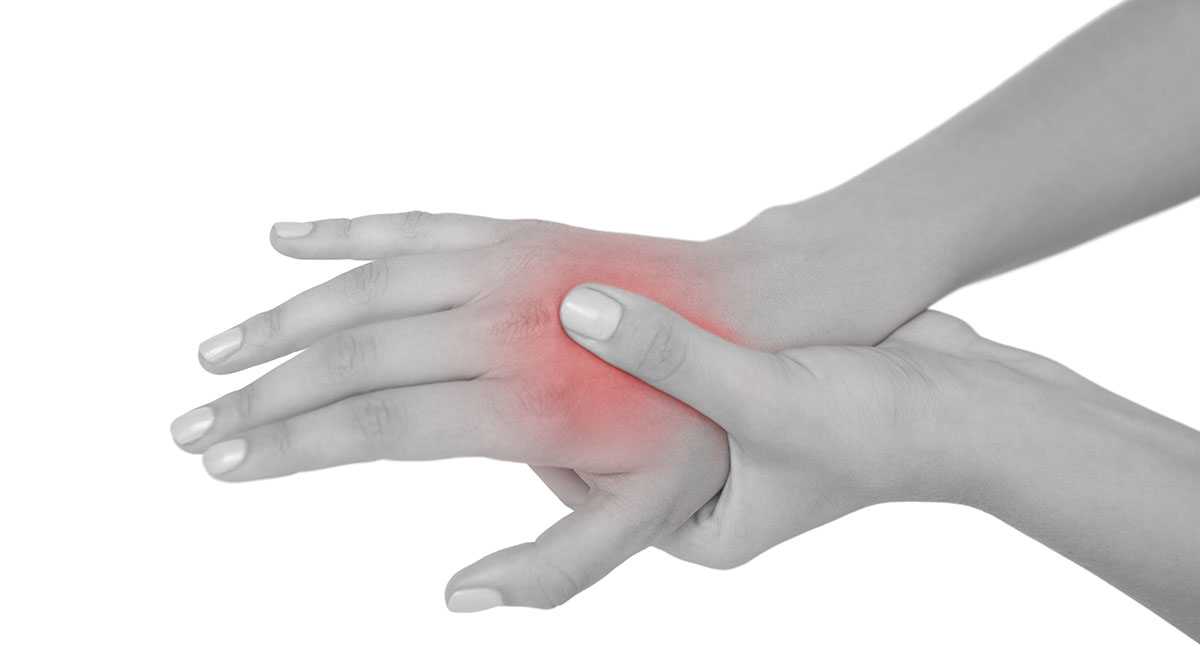

Τα χέρια είναι τα σημείο του σώματος που χρησιμοποιούμε περισσότερο, γι’ αυτό και κάθε πόνος ή άλλο σύμπτωμα μας κινητοποιεί άμεσα.

Πώς εκδηλώνεται

Αίσθημα καύσου, φαγούρα, «μυρμήγκιασμα» ή μούδιασμα στην παλάμη και στα δάκτυλα (ιδίως στον αντίχειρα, τον δείκτη και τον μέσο).

Τα συμπτώματα εκδηλώνονται στο ένα ή και στα δύο χέρια στη διάρκεια της νύχτας και εξελίσσονται σε «μυρμήγκιασμα» στη διάρκεια της ημέρας.

Η λαβή μπορεί να είναι αδύναμη και ο πάσχων να νιώθει έναν οξύ πόνο να διαπερνά τον καρπό και το χέρι του σε ορισμένες θέσεις.

Πιθανότερη αιτία

Η πιθανότερη αιτία είναι το σύνδρομο του καρπιαίου σωλήνα. Ο σωλήνας αυτός δημιουργείται από τα οστά του καρπού και περιέχει τους τένοντες και ένα νεύρο. Οι δραστηριότητες που περιλαμβάνουν επαναλαμβανόμενες, μονότονες κινήσεις, όπως η χρήση ηλεκτρονικού υπολογιστή, το βάψιμο κλπ. μπορεί να οδηγήσουν στην εμφάνισή του.

Αντιμετώπιση

Οι ασκήσεις του καρπού (λ.χ. ανοιγοκλείσιμο της γροθιάς με δύναμη και χαλάρωση εναλλάξ) και τα παυσίπονα μπορεί να βοηθήσουν.

Αν τα συμπτώματα είναι έντονα μπορεί να χρειασθούν αντιφλεγμονώδη, ενώ στις πιο σοβαρές περιπτώσεις απαιτείται χειρουργική θεραπεία.